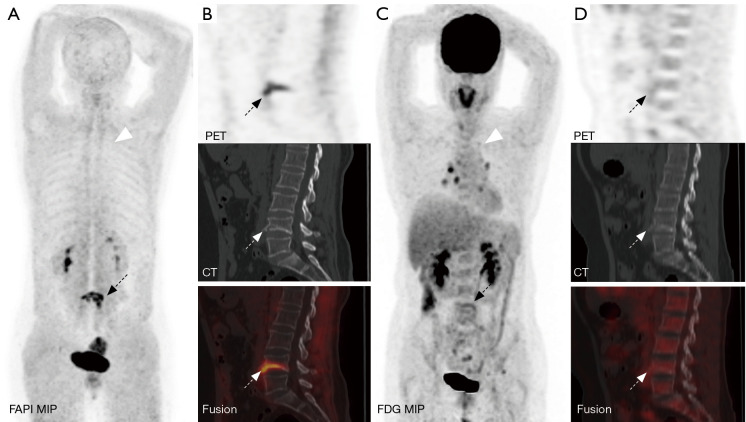

Background: Bone metastases of lung cancer typically indicate disease progression and poor prognosis. Early and accurate detection is crucial for staging, treatment planning, and prognostic evaluation. This study aimed to compare the diagnostic value of gallium 68-labeled fibroblast-activation protein inhibitor-04 ([68Ga]Ga-FAPI-04) and fluorine 18-labeled fluorodeoxyglucose ([18F]FDG) positron-emission tomography/computed tomography (PET/CT) imaging in detecting bone metastases in lung cancer.

Methods: A retrospective analysis was conducted on patients with pathologically confirmed lung cancer and clinically suspected bone metastases. These patients underwent both [68Ga]Ga-FAPI-04 and [18F]FDG PET/CT imaging. Initially, all patient images were visually evaluated, and the diagnostic efficacy of the two imaging methods was compared at both the patient and lesion levels for detecting bone metastases from lung cancer. Additionally, a semi-quantitative analysis was performed to compare the optimal maximum standardized uptake value (SUVmax) threshold and diagnostic efficacy of the two examinations for diagnosing benign and malignant bone lesions.

Results: A total of 25 lung cancer patients were included in the study, with nine confirmed cases and 133 lesions of bone metastases. At the patient level, there were no statistically significant differences in the detection rate, sensitivity, specificity, positive predictive value, negative predictive value, or accuracy between [68Ga]Ga-FAPI-04 and [18F]FDG PET/CT for identifying patients with bone metastases (P>0.05). At the lesion level, the detection rate, sensitivity, negative predictive value, and accuracy of [68Ga]Ga-FAPI-04 PET/CT for detecting bone metastases were higher than those of [18F]FDG PET/CT (81.37% vs. 57.14%, 98.50% vs. 69.17%, 88.24% vs. 34.92%, 90.68% vs. 70.81%), with statistically significant differences (P<0.01). The SUVmax of malignant bone lesions on both [68Ga]Ga-FAPI-04 and [18F]FDG PET/CT was significantly higher than those of benign bone lesions, with statistically significant differences (P<0.05). Moreover, the SUVmax of benign and malignant bone lesions on [68Ga]Ga-FAPI-04 PET/CT was significantly higher than those on [18F]FDG PET/CT, with statistically significant differences (P<0.01). In [68Ga]Ga-FAPI-04 and [18F]FDG PET/CT imaging, the area under the curves (AUCs) of SUVmax for diagnosing bone metastases were 0.856 and 0.724, respectively, with statistically significant differences (P<0.05); the optimal diagnostic thresholds were 5.38 and 3.77, respectively. The sensitivity, negative predictive value, and accuracy of SUVmax based on [68Ga]Ga-FAPI-04 PET/CT for diagnosing lung cancer bone metastases were higher than those based on [18F]FDG PET/CT (80.45% vs. 65.26%, 46.49% vs. 23.26%, 81.25% vs. 67.29%), with statistically significant differences (P<0.05).

Conclusions: Compared to [18F]FDG PET/CT, [68Ga]Ga-FAPI-04 PET/CT significantly improves the detection rate of lung cancer bone metastases at the lesion level. Additionally, [68Ga]Ga-FAPI-04 PET/CT offers superior image contrast and higher SUVmax, which also contribute to improving the accuracy of lung cancer bone metastasis diagnosis. This allows for more accurate staging of patients, enabling precise individualized treatment and improving patient prognosis.